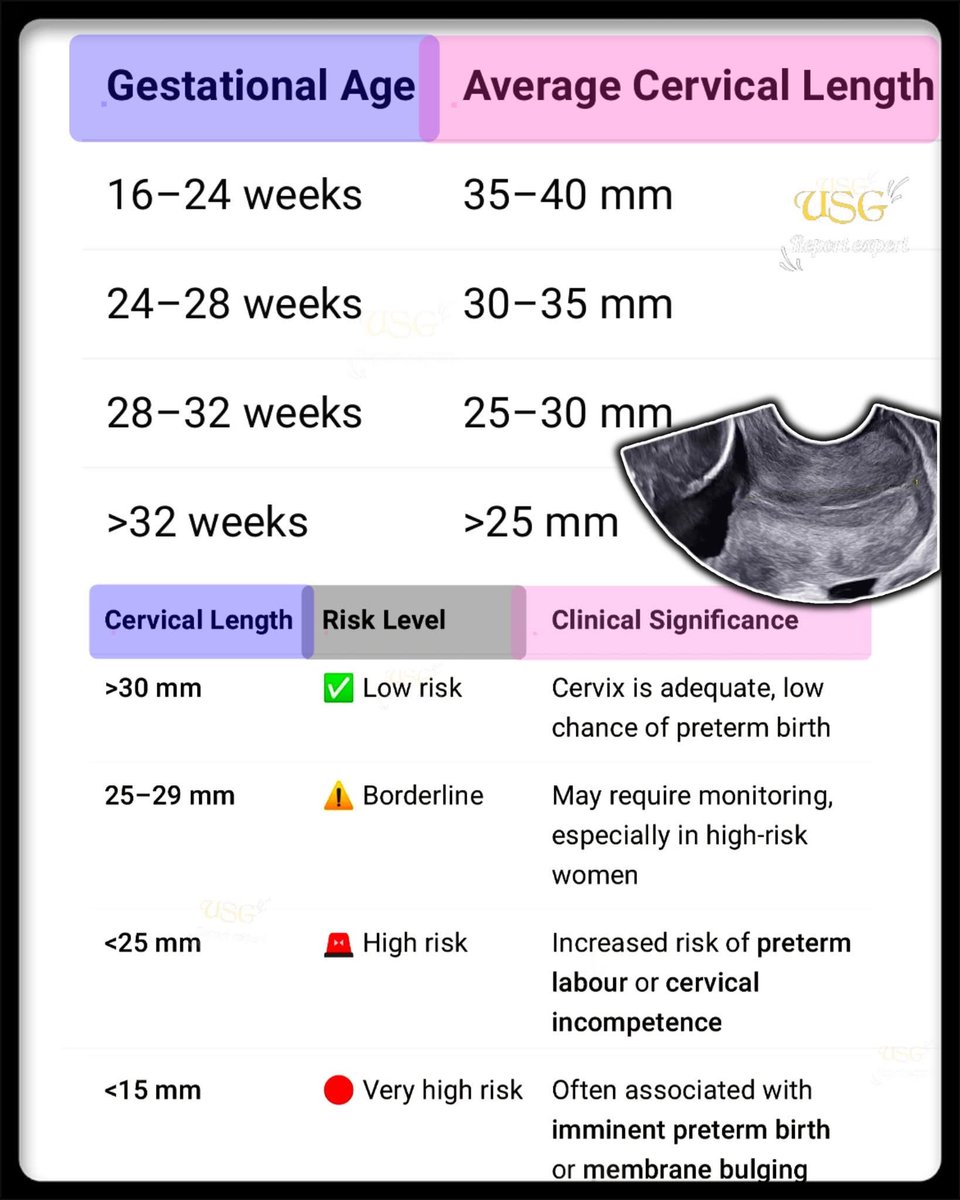

𝗖𝗘𝗥𝗩𝗜𝗖𝗔𝗟 𝗟𝗘𝗡𝗚𝗧𝗛 𝗜𝗡 𝗨𝗟𝗧𝗥𝗔𝗦𝗢𝗨𝗡𝗗 Normal Cervical Length : ≥25 mm Risk starts : <25 mm Serious risk : <15 mm #EchoTech

𝗖𝗘𝗥𝗩𝗜𝗖𝗔𝗟 𝗟𝗘𝗡𝗚𝗧𝗛 𝗜𝗡 𝗨𝗟𝗧𝗥𝗔𝗦𝗢𝗨𝗡𝗗 Normal Cervical Length : ≥25 mm Risk starts : <25 mm Serious risk : <15 mm #EchoTech

𝗖𝗘𝗥𝗩𝗜𝗖𝗔𝗟 𝗟𝗘𝗡𝗚𝗧𝗛 𝗜𝗡 𝗨𝗟𝗧𝗥𝗔𝗦𝗢𝗨𝗡𝗗 Normal Cervical Length : ≥25 mm Risk starts : <25 mm Serious risk : <15 mm #EchoTech